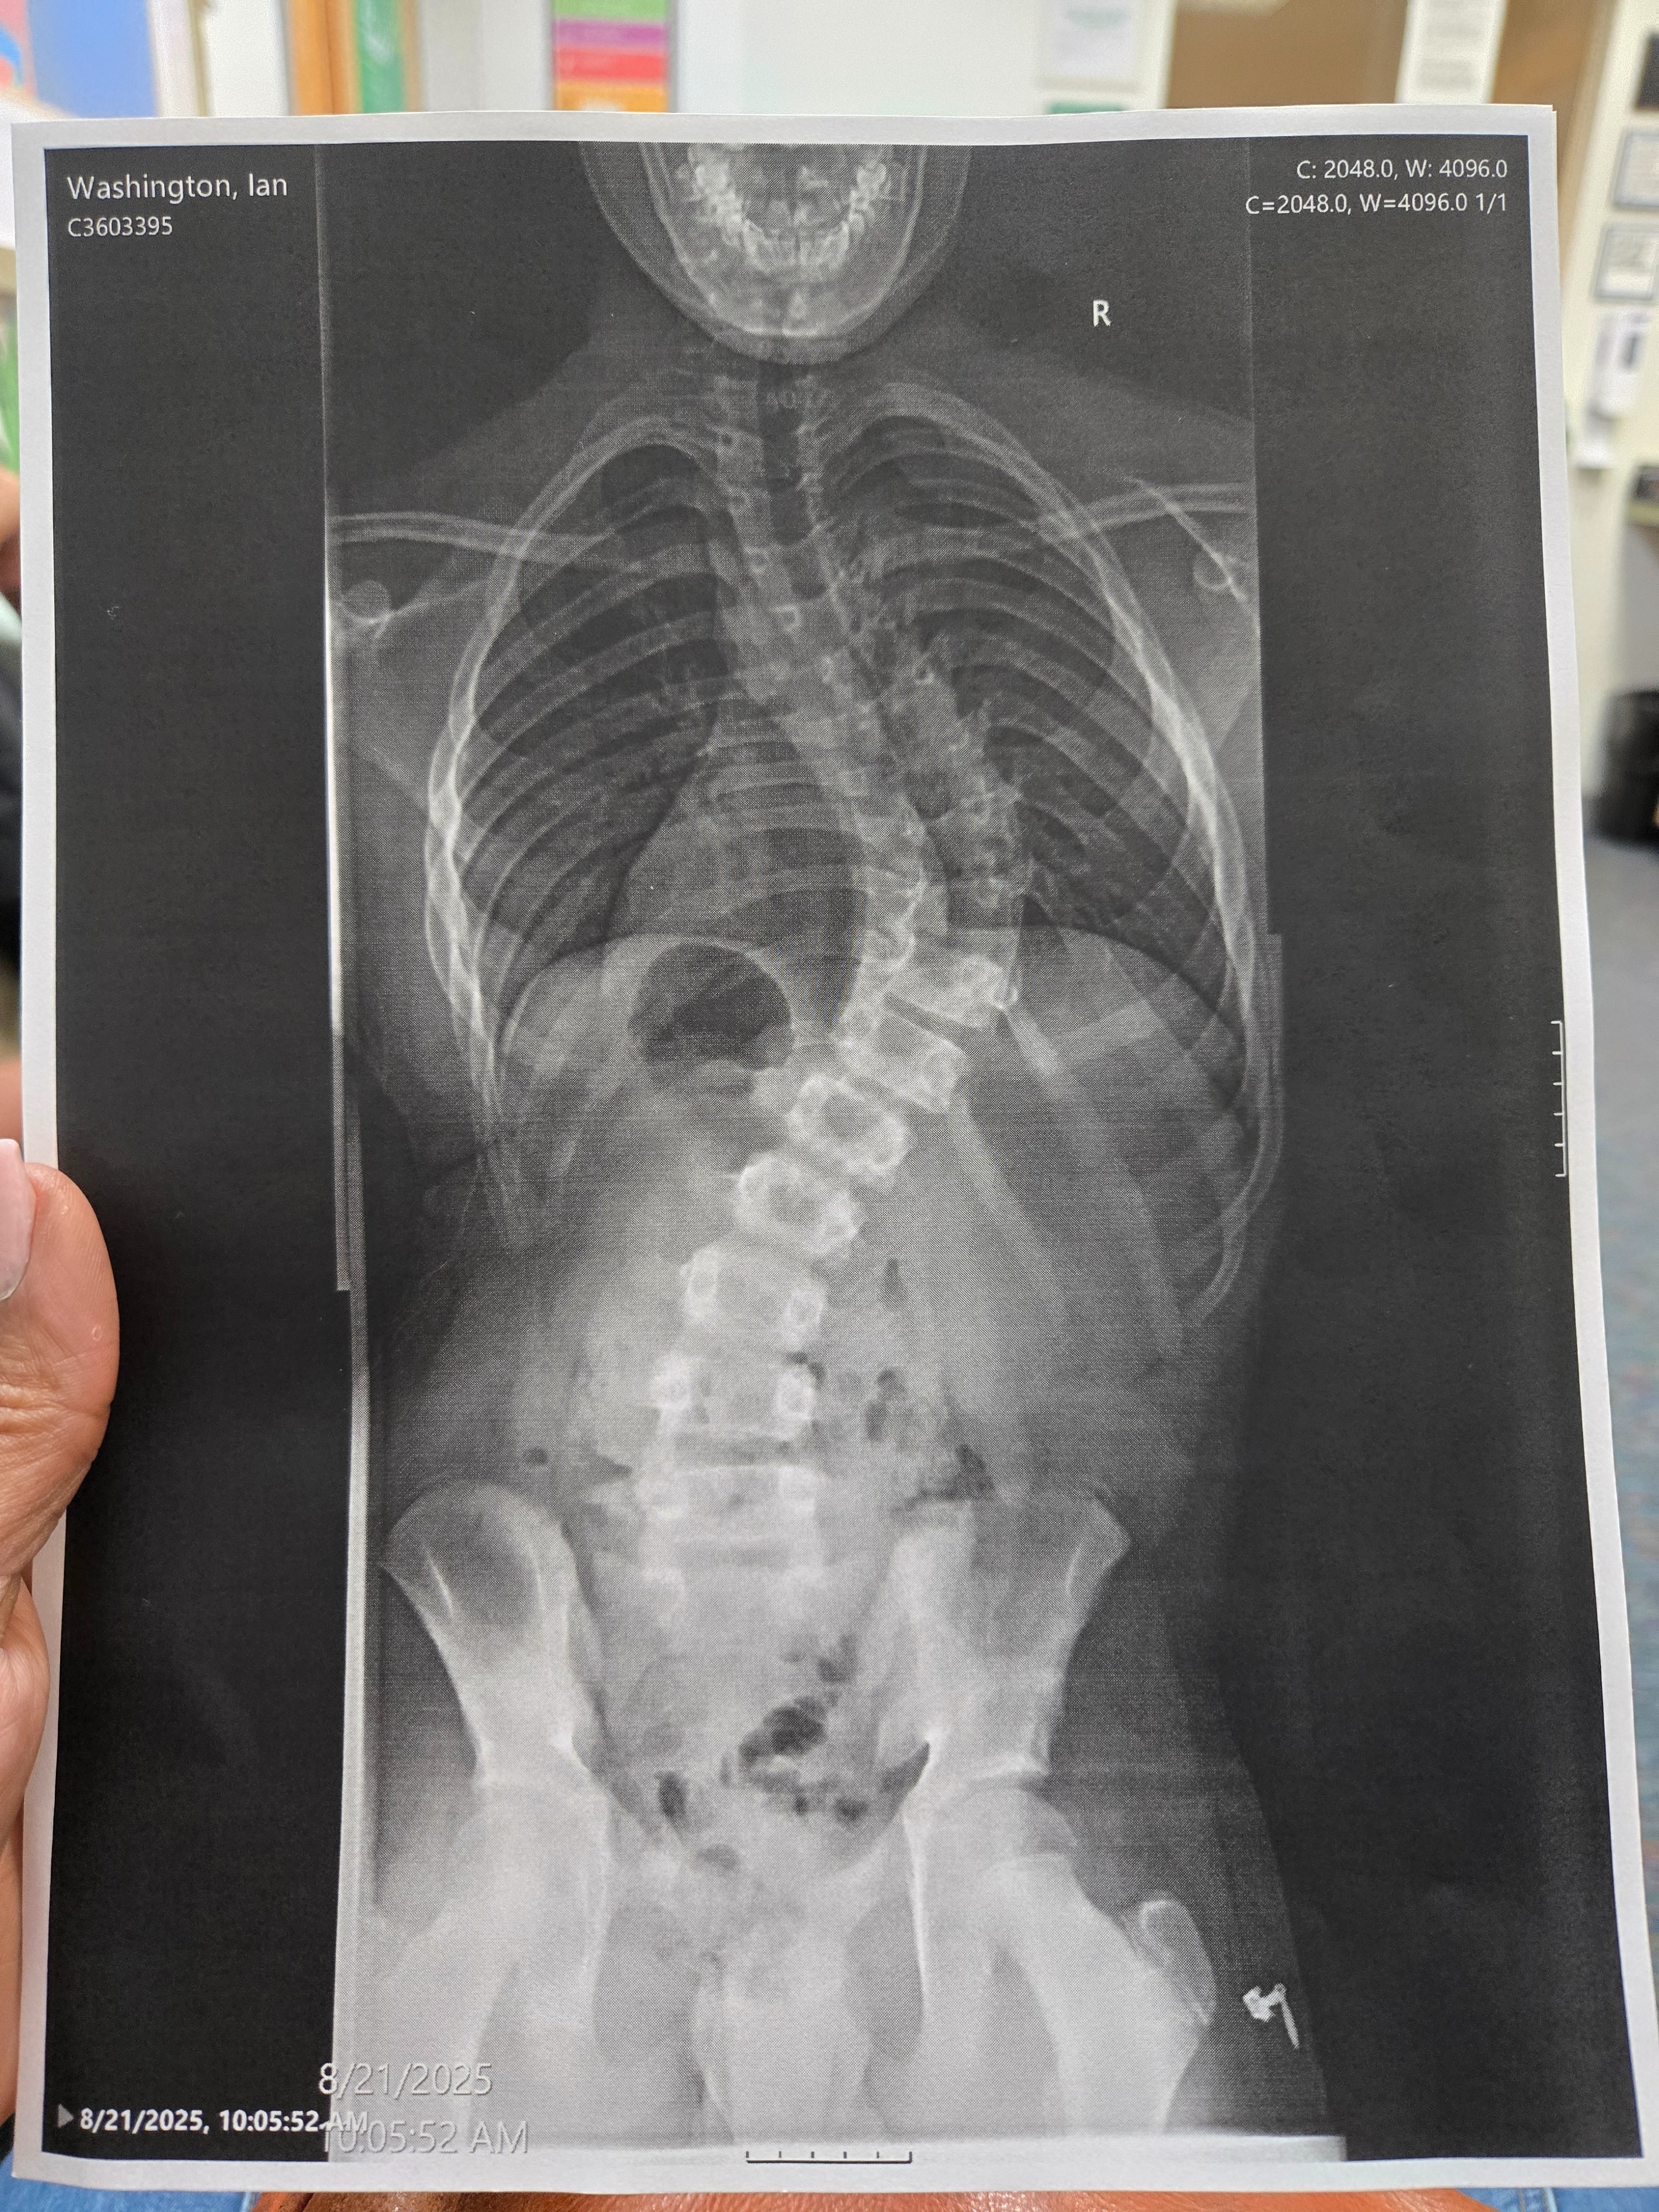

Our youngest son, Ian, has been diagnosed with severe scoliosis and is requiring a major spinal surgery due to his continuous back pain. He is a wonderful and active 12-year-old that has been dealt a crappy hand, but we—his family—are his backup. He has worn a sleeping back brace since January; however, this did not improve his pain level or slow down the curvature. So he now has a 70° curve, but he was only at a 47° curve at the beginning of the year. He has now been prescribed a daytime brace to give him a little relief at school, but that still will not take his pain away. We have been working with his school to accommodate him wherever possible, but his pain has caused him to miss a number of days from school. So now, homebound care is the next step until his surgery and recovery is complete, so that he doesn't fall behind in his schoolwork.